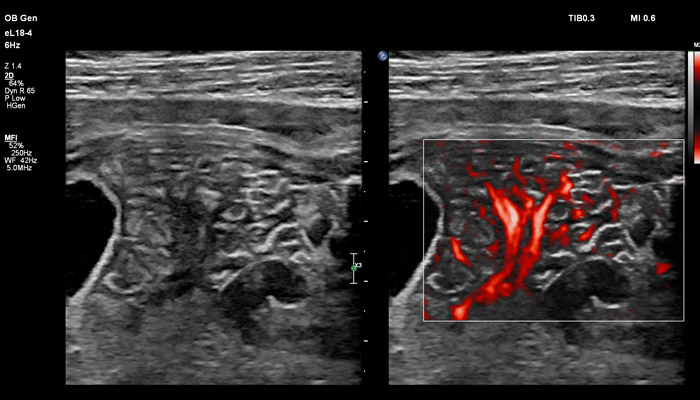

В случае аномалий позвоночника, оценка ануса важна, чтобы исключить аноректальные пороки развития, которые могут быть частью более широкой группы аномалий, известных как VACTERL (аномалии позвоночника, атрезия ануса, пороки сердца, трахеопищеводный свищ, аномалии почек, дефекты лучевой кости). Исследования в США показали, что очень высокое качество изображений еL18-4 повышают уверенность клиницистов в исключении аноректальной аномалии плода. Точная оценка состояния плаценты важна при определении сроков родоразрешения, а также при планировании хирургических вмешательств. Изображения показывают нормальный миометрий и четкую границу с плацентой. С визуализацией микрокровотока (MFI) хорошо представлены дугообразные артерии матери, спиральные артерии, а также ветвящиеся ворсинчатые артерии, что подтверждает нормально развитую сосудистую систему. Клинические исследования, проведенные экспертами детской больницы штата Аризона (США) во главе с Д-ром Льюсом Гонкалвсом с целью определения наличия нормальной сосудистой структуры плаценты при подозрении на ее патологию, показали, что инновационная технология сверхширокополосной PureWave матрицы датчика eL18-4 способна изменить привычный способ, которым врачи интерпретируют нормальный и аномальный сосудистый поток в плаценте.

Линейный матричный датчик eL18-4 поддерживает режим высокочувствительной визуализации кровотока (Philips MicroFlow Imaging), новый запатентованный метод, который обеспечивает инновационный подход к оценке сосудистого русла. Визуализация MicroFlow преодолевает многие барьеры, связанные с традиционными методами обнаружения кровотока в малых сосудах, обеспечивая высокое разрешение при минимальных артефактах. Метод MicroFlow Imaging поддерживает высокую частоту кадров и качество изображения, применяет инновационные методы сокращения артефактов. Варианты вычитания 2D-изображений, смешивания и параллельного отображения обеспечивают превосходную визуализацию в различных клинических случаях.